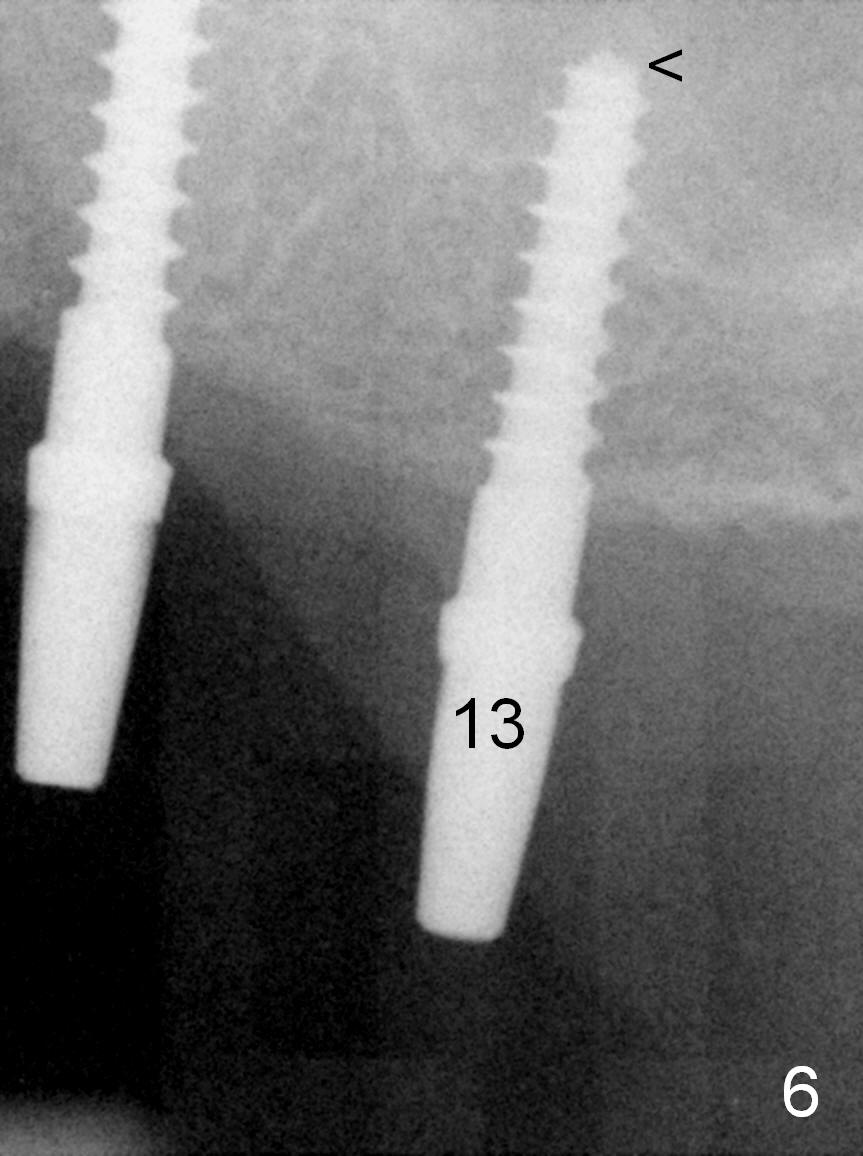

When the patient returns for implant placement (2nd visit after initial exam), he reveals that he is a dental phobic.  He requests placement of 4 implants in the upper left quadrant, instead of 2.  Narrow ridge is unexpected in the canine and premolar area (Fig.1).  Limited bone height at #13 (Fig.3 arrowheads: sinus floor) is found when initial drills are in place (Fig.2,3).  A 2-piece implant (4.5x17 mm tissue-level) is placed at #10 after extraction, while 1-piece implants are placed at 11 (3x17 mm (tissue-level, 15 °) and 12 and 13 (bone-level, 2.5x14, 12 mm, respectively; Fig.4,5).  In fact the 1 piece implant at #13 is not completely placed (Fig.5).  It is removed, the apical 3 threads are cut off (Fig.6 <, since a shorter implant was unavailable in the office) and the remaining implant is re-inserted.  The insertion torques of the 4 implants are ~ 60, ~ 35, < 35 and 15 Ncm, respectively.  After adjustment (Fig.7), immediate provisionals are fabricated at #10 and 11 (Fig.8, later splinted with composite), while perio dressing is applied around the implants at #12 and 13 and the provisionals at #10 and 11.  There is no nasal hemorrhage postop.  Although the perio dressing is loose 1 week postop (Fig.9), it is not removed.  When the upper lip fissure (Fig.9 <) heals, provisionals at #12 and 13 are planned to be splinted to the other two ones.  Two weeks postop, the upper lip fissure heals, the perio dressing dislodges and the implants at #12 and 13 are stable (Fig.10).  After abutment height adjustment, a splinted provisional is fabricated over these 2.5 mm 1-piece implants (Fig.11).